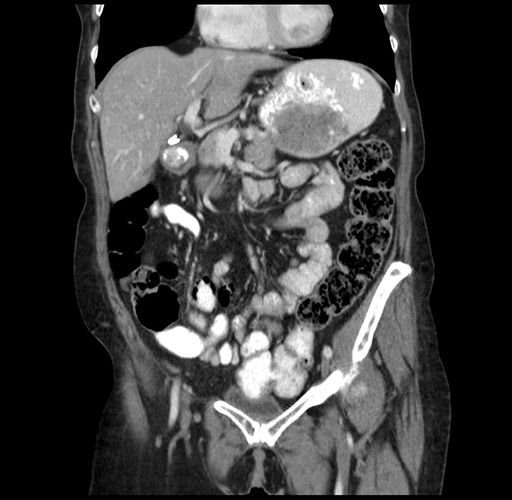

Pre-Chemo: Coronal Venous